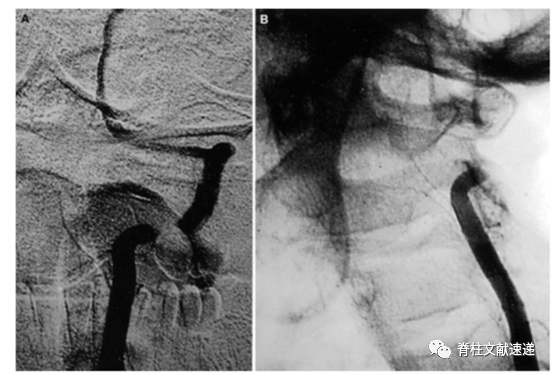

2)单纯松解术:椎动脉在某处存在骨性或软性(韧带)狭窄导致BHS,可通过单纯松解来实现。如下图所示。

图注:如上图所示:颈前入路,下颌下横切口。显露颈2、3椎体,切除症状侧部分颈长肌,从腹侧切开症状侧C2椎动脉孔,游离椎动脉V3下段,微型彩超术中观察转头后椎动脉无闭塞。术后DSA(图C)确认解除动态性椎动脉闭塞。